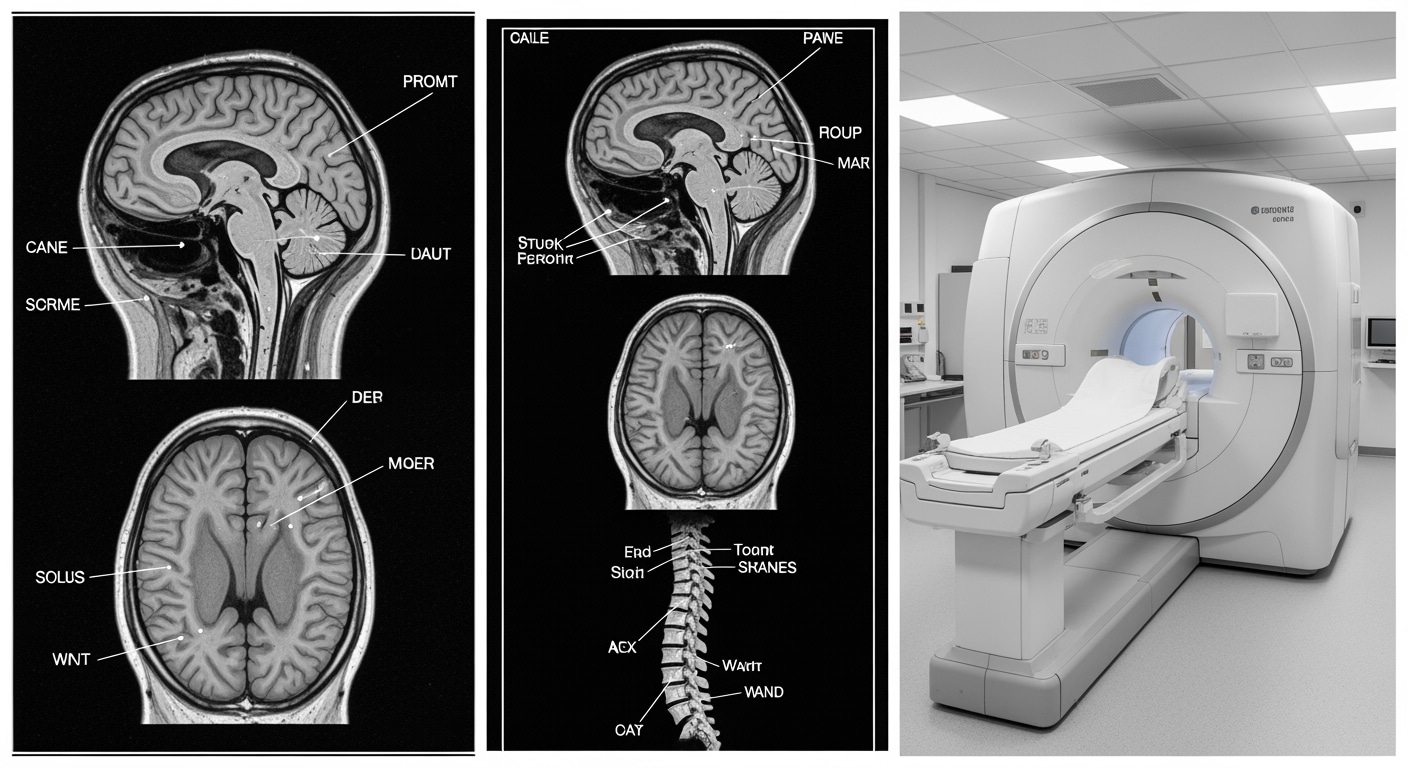

State-of-the-art 1.5 Tesla MRI equipment available 24/7 at Priority ER

MRI Process at Priority ER: Zero Wait Neurological Imaging

Upon arrival at Priority ER for emergency MRI evaluation, patients wondering "do emergency rooms do MRI" receive immediate confirmation through our zero-wait protocol. Board-certified emergency physicians trained in neurological emergencies begin assessment within minutes, utilizing 1.5 Tesla MRI technology that produces detailed brain, spine, and soft tissue images with resolution exceeding 1mm[9]. This comprehensive approach identifies acute ischemic stroke, hemorrhagic transformation, spinal cord compression, and subtle brain injuries that CT scans frequently miss.

Board-certified radiologic technologists providing immediate MRI imaging

Advanced MRI technology detecting acute stroke and brain injuries

Priority ER's MRI capabilities answer the question "do emergency rooms do MRI" by exceeding Joint Commission standards for emergency departments[14], featuring 1.5 Tesla technology typically found only in specialized neurology centers. Our MRI system produces images with submillimeter resolution, enabling detection of acute ischemic stroke within minutes of symptom onset, small vessel disease, microhemorrhages, and subtle traumatic brain injuries invisible on CT scans[15]. The integration of advanced protocols including diffusion-weighted imaging (DWI), susceptibility-weighted imaging (SWI), and MR angiography (MRA) allows comprehensive stroke evaluation within 20 minutes of scan initiation.